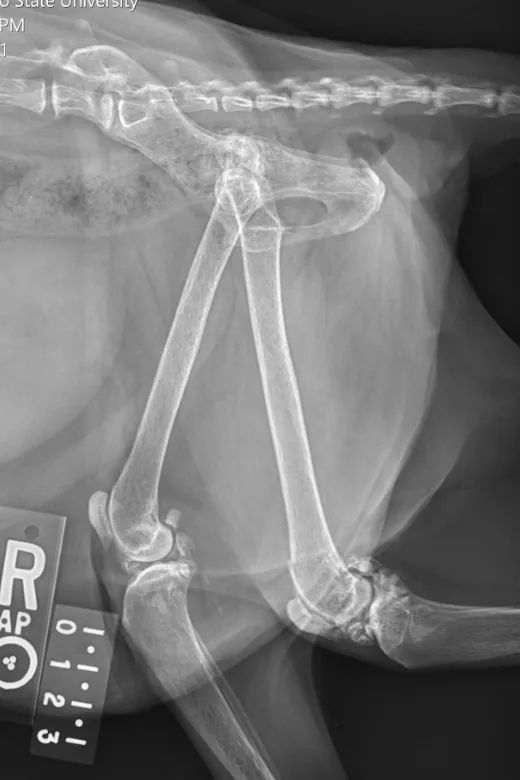

Radiographs taken by the referring clinician showed a shallow right acetabulum with decreased coverage of the femoral head and secondary changes, including a sclerotic acetabular rim, smoothly marginated periosteal proliferation along the cranial and caudal pillars of the acetabulum, flattening of the right femoral head, thickening of the femoral neck, and mild craniodorsal subluxation. The left coxofemoral joint was congruent but had mild changes with osteophytes along the cranial acetabular margin. There was a mild amount of spondylosis deformans at L6-L7 and L7-S1. Radiographs of the stifles showed subchondral bone sclerosis of both medial femoral condyles and medial tibial condyles. Osteophytes and enthesophytes were present along the distal femurs and proximal tibiae. A large amount of amorphous periarticular new bone was located within and adjacent to the craniomedial aspects of the stifle joints and just proximal to the tibial eminences. Radiographic diagnoses at that time were moderate, right-sided, coxofemoral degenerative joint disease with subluxation of the femoral head; mild, left-sided, coxofemoral degenerative joint disease with no evidence of subluxation; and severe, bilateral stifle degenerative joint disease.At the referral clinic, 8.5 months after initial presentation, Max was sedated, and repeat ventrodorsal and orthogonal lateral pelvic radiographs were obtained to evaluate progression or change (Figure).

Ventrodorsal and lateral pelvic radiographs showing severe osteophyte formation along the right femoral head and neck that caused effacement of the trochanteric fossa. The acetabulum is shallow due to remodeling and osteophyte formation. Mild osteophyte formation remains along the left femoral head and neck, as well as moderate osteophyte formation along the acetabulum. Caudal lumbar spondylosis deformans is unchanged from initial radiographic findings. Rounded, angular mineral bodies are present bilaterally in the stifle joints with moderate concurrent periarticular osteophyte formation. Short, linear mineral bodies can be seen in the soft tissues of the right caudal crus.

Although findings were unchanged from previous radiographs, OA in the right hip appeared mildly progressed.